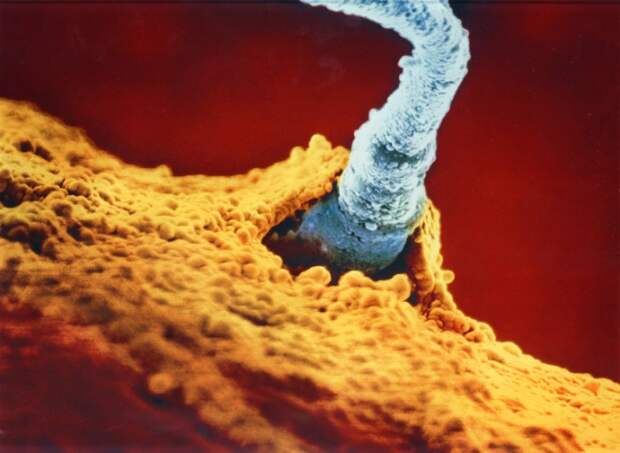

4. Один из 200 миллионов отцовских сперматозоидов прорвал оболочку яйцеклетки.